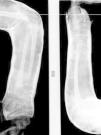

Presentamos el caso de un paciente varón de 4 años de edad, que consulta a nuestro servicio de Urgencias por caída casual desde una escalera. Presenta dolor y deformidad dorsal en el antebrazo izquierdo. En la radiografía simple de antebrazo se visualiza una deformidad plástica dorsal y radial en el cúbito y el radio (fig. 1).

En el caso que presentamos, la deformidad presentaba un ángulo de 34°; se realizó reducción cerrada bajo sedación con Kalinox®. El control radiológico (fig. 2) fue correcto, así como el control evolutivo a las 4 semanas.